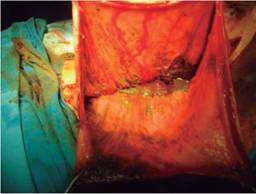

En la radiografía simple de abdomen, se apreciaba una imagen correspondiente al colon sigmoides, el cual se observó con abundante materia fecal en su interior y abarcaba la totalidad de la cavidad abdominal, con borramiento de la silueta hepática e imagen en vidrio despulido (Figura 2). En la radiografía de tórax, se apreció el hemidiafragma izquierdo desplazado cefálicamente por un asa intestinal (Figura 3). Se realizó laparotomía exploradora, donde se encontró sigmoides a tensión con pared intestinal engrosada, abarcando la totalidad de la cavidad abdominal (Figura 4), manteniendo el resto del intestino desplazado de manera posterior, el hígado y bazo hacia la región superior del abdomen y el diafragma izquierdo elevado. Se realizó colotomía descompresiva y se drenó abundante materia fecal y gas (Figura 5); se procedió a la hemicolectomía izquierda y se dejó colostomía del transverso. El paciente fue ingresado a terapia intensiva por choque hipovolémico grado III y sepsis abdominal; evolucionó de manera tórpida y sin gasto a través de la colostomía. Requirió de una nueva intervención al sexto día, y presentó nueva dilatación del colon transverso y ascendente, por lo que se realizó colectomía total con ileostomía. Fue manejado de forma conservadora; egresó a los 10 días de la terapia intensiva y a los 18 días de piso de cirugía con la ileostomía funcional.